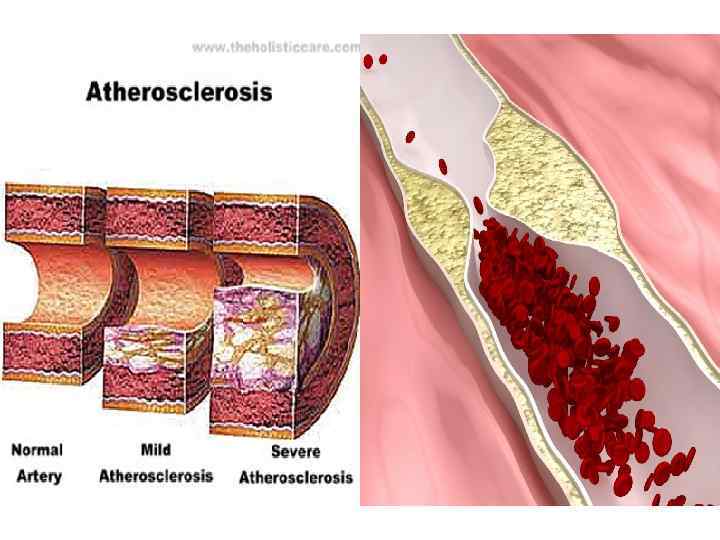

ЭПИДЕМИОЛОГИЯ. • Заболеваемость стенокардии напряжения увеличивается с возрастом. У мужчин она возрастает с 2 -5% в возрасте 45 -55 лет до 11 -20% в возрасте 65 -75 лет. У женщин соответственно с 0, 5 -1% до 10 -14%. • С возрастом утяжеляются клинические проявления стенокардии. Наиболее часто наблюдается СН II-III ФК. • СН как клинический синдром наблюдается у 2025% пациентов старше 75 лет. • Стенозирующий атеросклероз у пожилых людей встречается в 50 -70% аутопсий.

МЕДИКАМЕНТОЗНОЕ ЛЕЧЕНИЕ (8). • Гиполипидемическая терапия. Статины. Являются обязательным компонентом лечения пациентов с стенокардией. Уменьшение летальности от осложнений ИБС и частоты развития ИМ происходит пропорционально снижению уровня ХС и ХС ЛНП. Успешная коррекция нарушений липидного обмена вместе с воздействиями на другие ФР ИБС существенно улучшает результаты антиангинальной терапии и заметно повышает качество жизни пациентов с ИБС. В то же время применение статинов в пожилом и старческом возрасте менее целесообразно, чем в среднем, поскольку на кальцинированные атеросклеротические бляшки они не влияют. Их назначение обосновано при высоком уровне ХС и ХС ЛНП, особенно после хирургической коррекции КА.